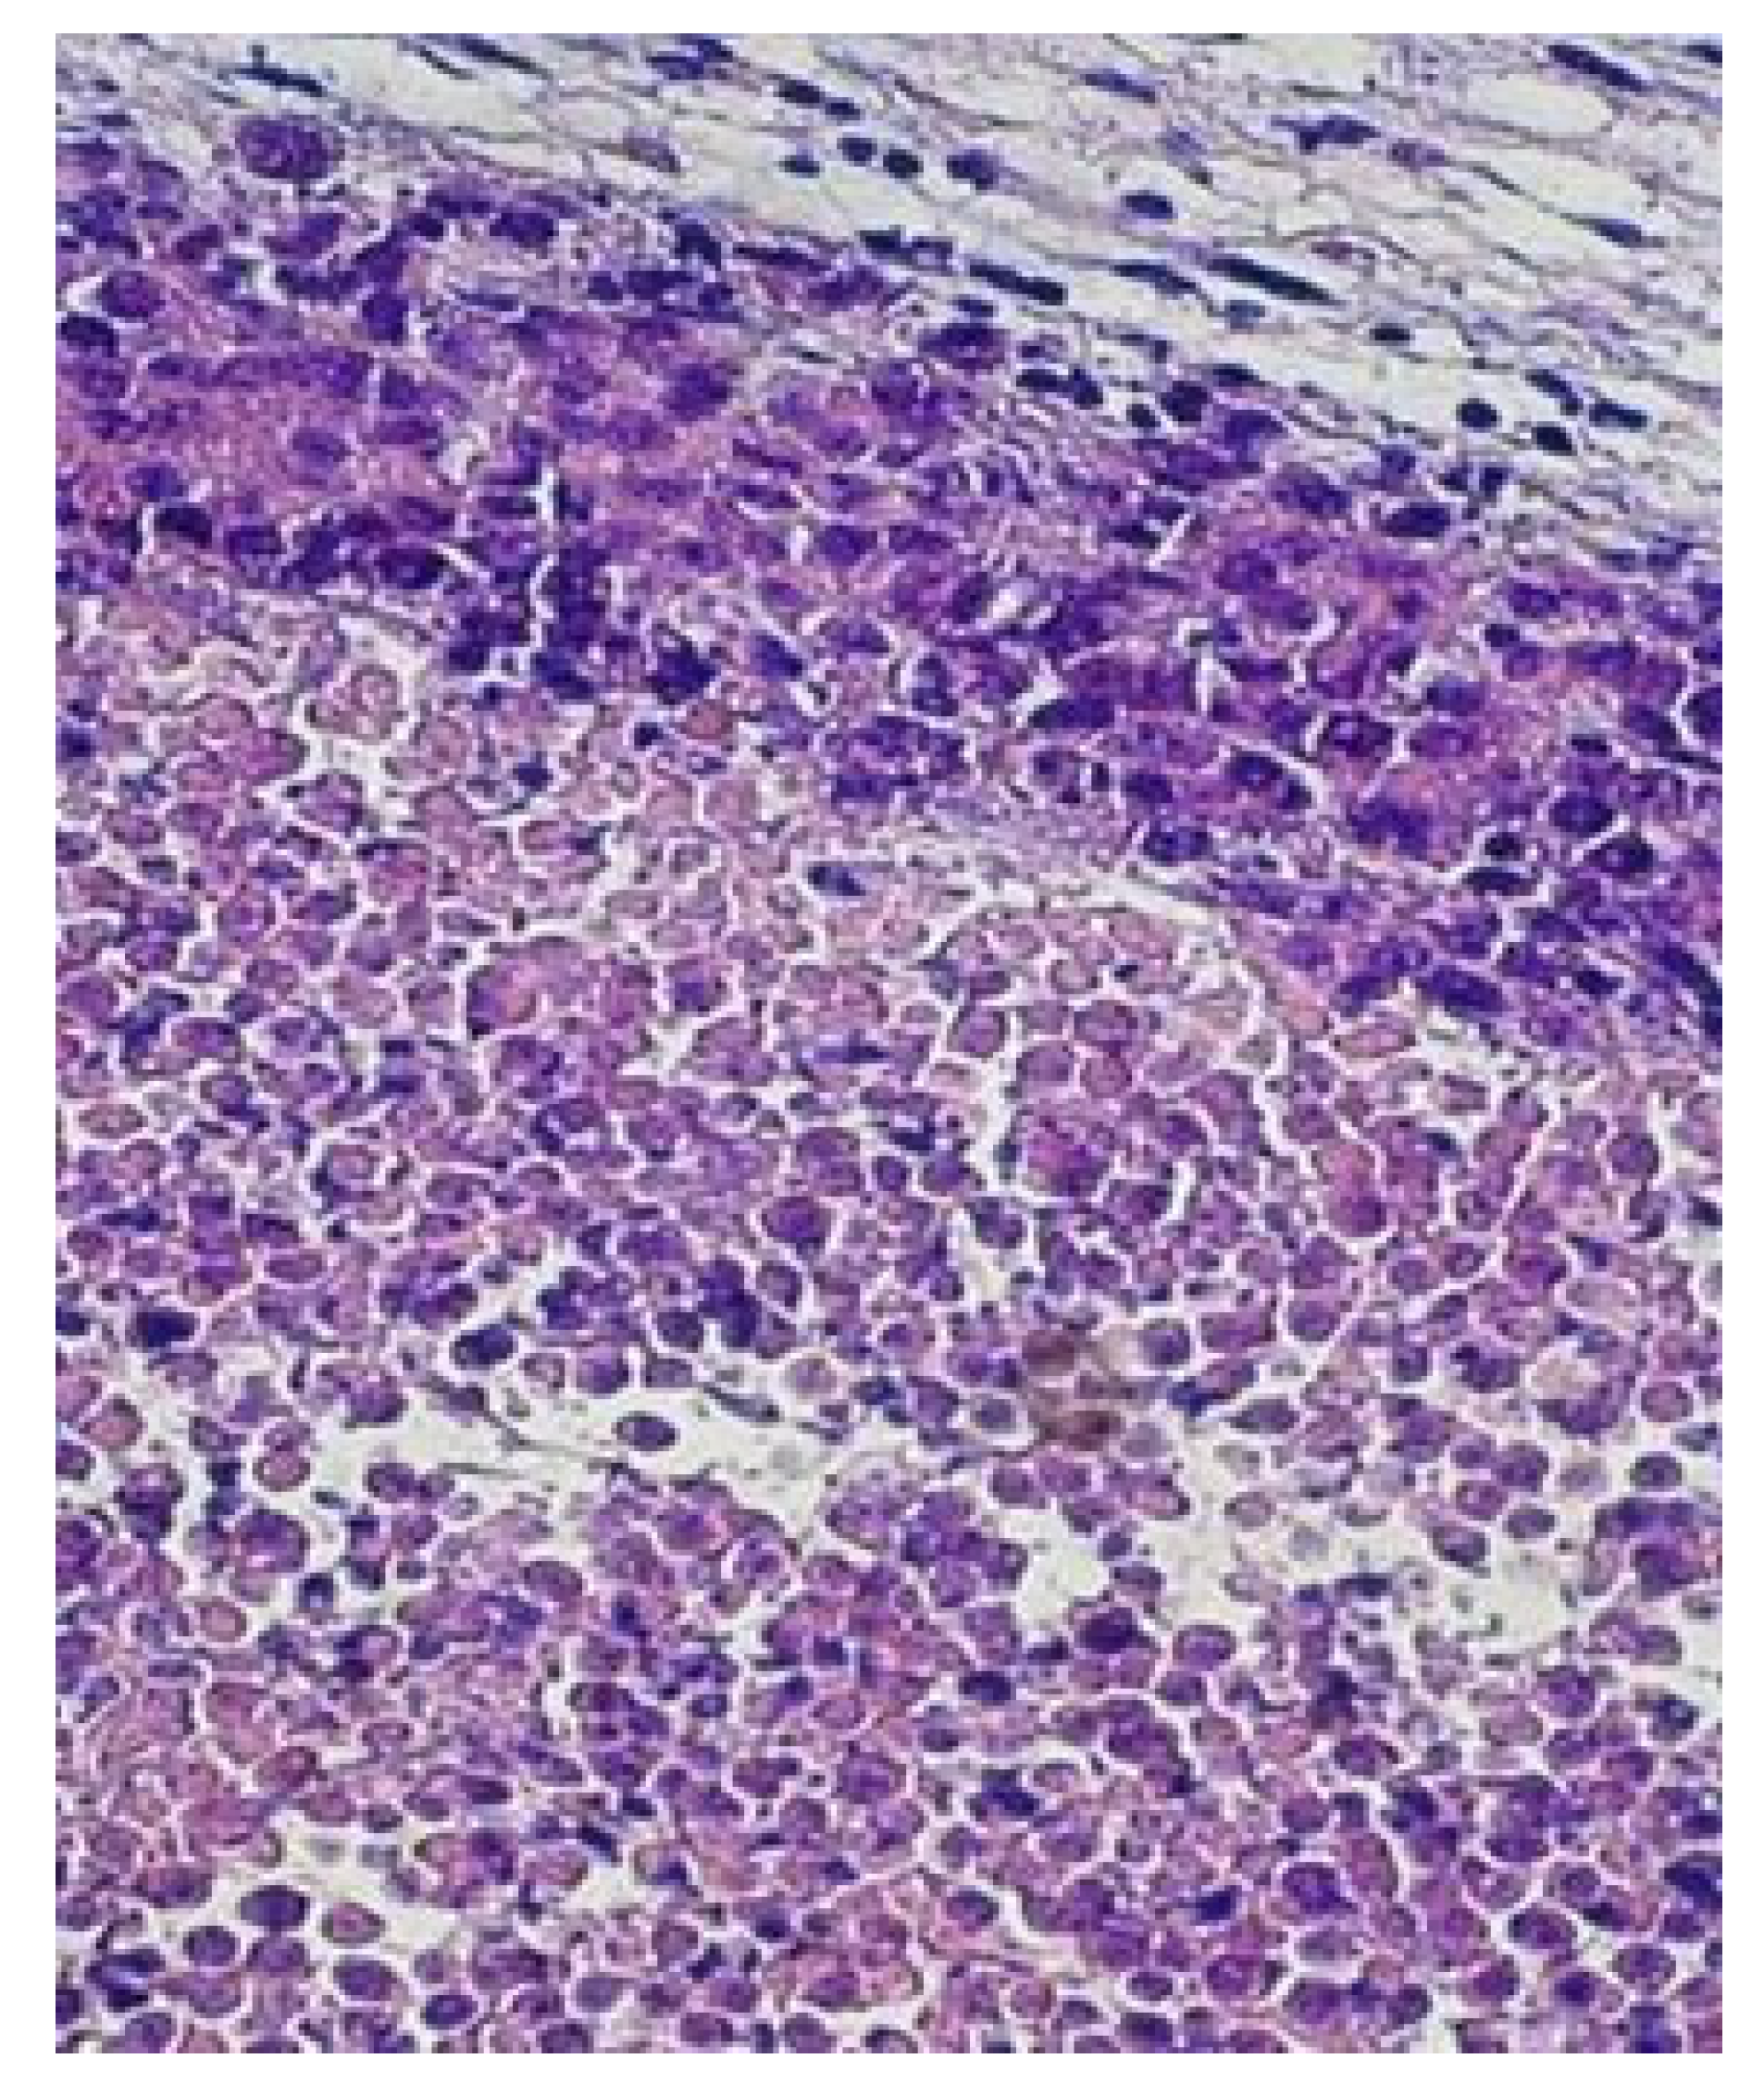

3.2.1. Control: Group I

3.2.2. Group II: Mice Vaccinated with EcPHL Immune Modulator

- Histological analyses of the EcPHL-treated mice tumor tissue samples (see Figure 5, Figure 6, Figure 7 and Figure 8) show an increased number of macrophages (supposedly M1 phenotype), which, in turn, release cytokines (e.g., IL-12, TFN-α, and IFN-γ), stimulate further immune system responses, specifically in and around the tumor lesions, and promote tumor cell killing. The observed EcPHL efficacy and the effect of the macrophages on Ehrlich carcinoma are consistent with the view that M1 macrophages possess anti-tumor properties [24,47,48,49].